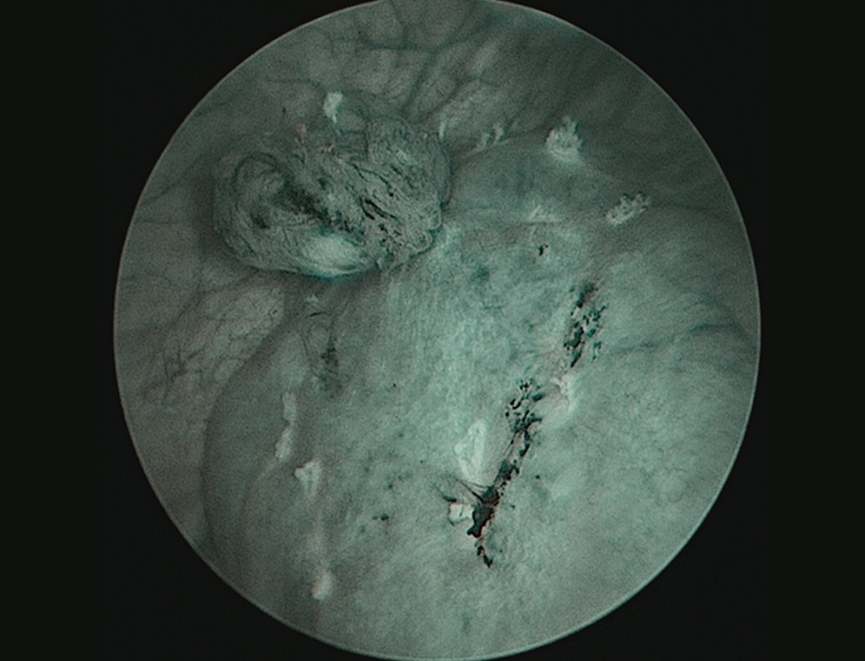

通过我们的研究,我们认为应用BT-ESD技术治疗肿瘤直径1~3 cm低危膀胱尿路上皮癌,有较好的安全性与可行性,而且肿瘤预后也可能优于TURB,其原因可能和肿瘤被完整切除并取出,减少了可能的残留或种植的风险[6];术中注射形成的水垫、清晰的层次,保证了切除深度在粘膜下层以下,降低了因经验不足,切除深度不够的可能[7]。而且,相比较TURB,BT-ESD技术能够减少严重并发症的发生率,特别当肿瘤位于膀胱侧壁或输尿管口附近时。此外,术后清晰详尽的病理(边缘有无肿瘤、粘膜固有层或肌层有无浸润)较TURB破碎、因烧灼焦痂无法辨识的病理,更能为如何决策后续治疗(是否行二次电切、是否行持续灌注)提供证据。(图2)

图2-aBT-ESD切除标本基底部病理(x40)

图2-b TURB切除标本基底部病理(x40)

图2.BT-ESD切除标本与TURB切除标本基底部病理比较